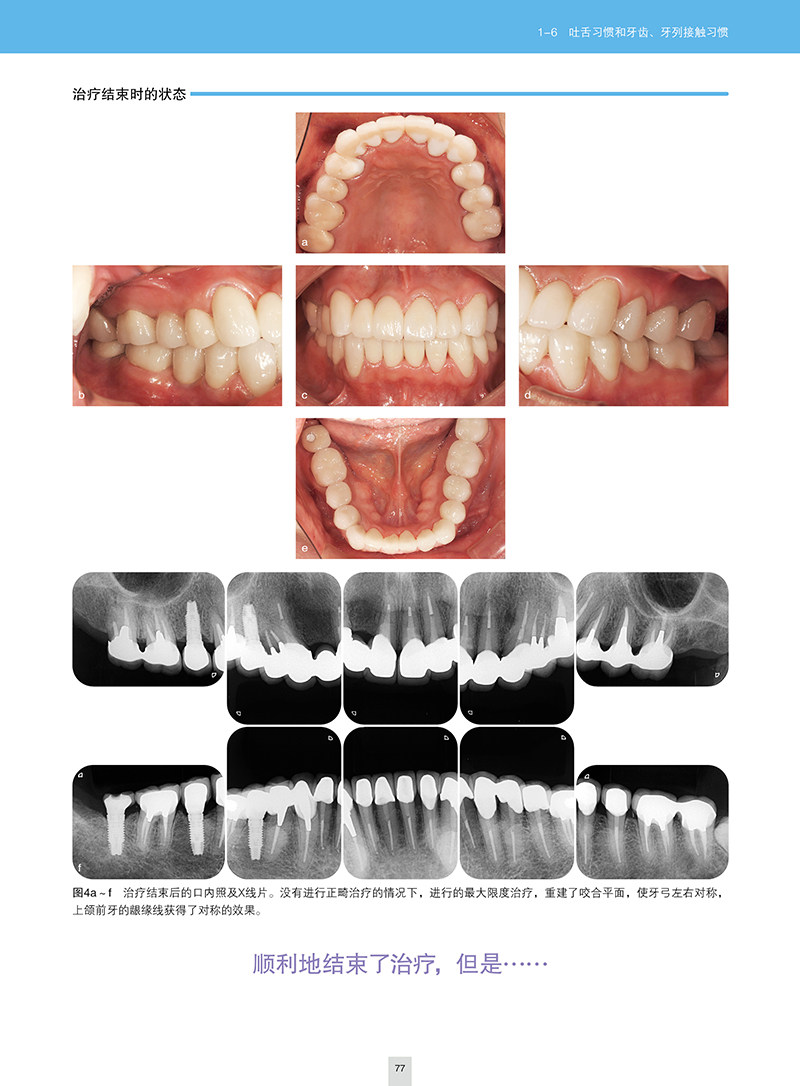

1-6 吐舌习惯和牙齿、牙列接触习惯 74

01 患者美观需求高的话 74